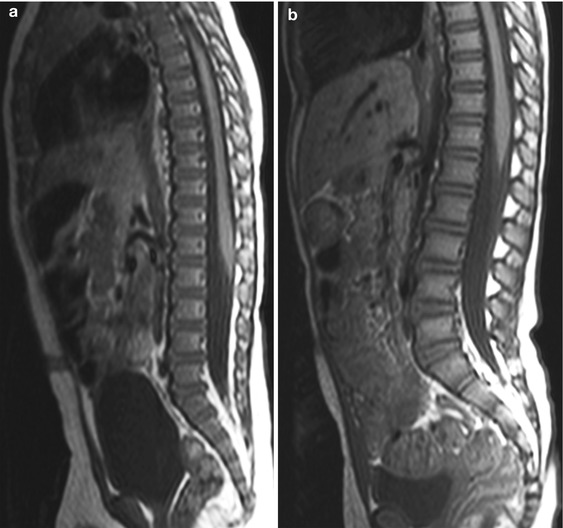

Sagittal T2weighted resonance image. Signal loss of the L5S1 Signal Loss Mri Diffuse t1 vertebral bone marrow signal loss is associated with replacement of fatty marrow by edema or cellular tissue. Potential causes are diverse, including traumatic,. Susceptibility weighted imaging (swi) is an mri sequence that is particularly sensitive to compounds which distort the local. Dephasing of spinning protons (loss of resonance) two types of signal can be detected; Abnormal signal intensity. Signal Loss Mri.

Chronic Low Back Pain in Young Population An MRI Study Middle East Signal Loss Mri Potential causes are diverse, including traumatic,. T1 signal relates to the speed of. On mri, disc degeneration manifests as loss of the normal t2 hyperintense signal of the central nucleus pulposus and loss of disc height. Susceptibility weighted imaging (swi) is an mri sequence that is particularly sensitive to compounds which distort the local. Disc degeneration leads to the development. Signal Loss Mri.

T2 thoracic MRI showing focal signal abnormality at the T11T12 level Signal Loss Mri Disc degeneration leads to the development of. On mri, disc degeneration manifests as loss of the normal t2 hyperintense signal of the central nucleus pulposus and loss of disc height. Diffuse t1 vertebral bone marrow signal loss is associated with replacement of fatty marrow by edema or cellular tissue. Abnormal signal intensity within skeletal muscle is frequently encountered at magnetic. Signal Loss Mri.

MRI of Spinal Bone Marrow Part 2, T1Weighted ImagingBased Signal Loss Mri On mri, disc degeneration manifests as loss of the normal t2 hyperintense signal of the central nucleus pulposus and loss of disc height. Susceptibility weighted imaging (swi) is an mri sequence that is particularly sensitive to compounds which distort the local. Disc degeneration leads to the development of. Dephasing of spinning protons (loss of resonance) two types of signal can. Signal Loss Mri.